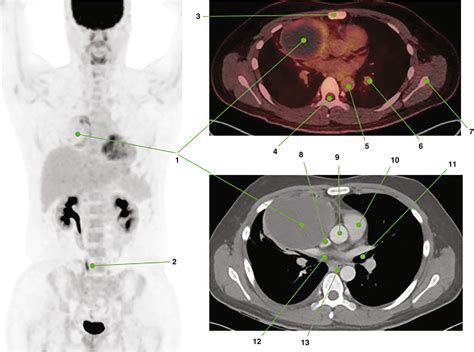

At its core, a Pet Ct scan is designed to provide both functional and structural information. While a traditional CT scan uses X-rays to create detailed pictures of organs and tissues, a PET scan uses a small amount of radioactive tracer to highlight areas of high metabolic activity. This is particularly crucial in oncology, as cancer cells often exhibit higher metabolic rates than healthy cells.

When these two technologies are combined into a single Pet Ct machine, the results are fused together. This allows doctors to pinpoint the exact location of a biological abnormality and observe its physical size and shape simultaneously. The fusion of this data is what makes it a gold standard in modern diagnostics.